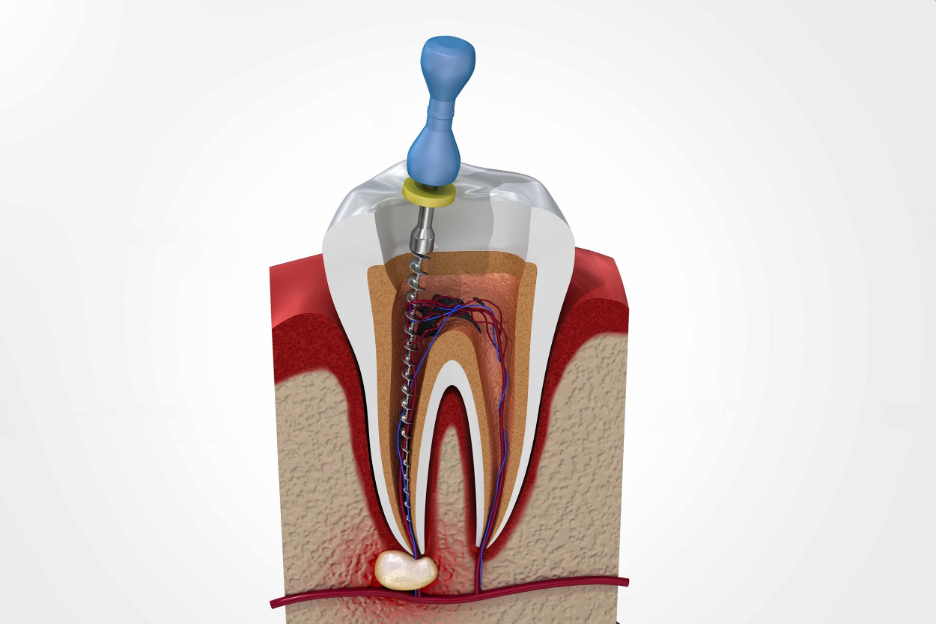

● In the next step, the tooth is opened by cutting burs by using a handpiece to access the canals with endo files, and pus is drained in case of an abscess or infection.

● The infected pulp is removed from the canals, which makes the tooth dead and pain free.

● The canals inside the root are cleaned and shaped with tiny instruments called files in single and multiple visits, followed by the root canals are sealed with gutta-percha points or root canal paste in baby teeth. This process is called obturation.

● After the filling of roots, the tooth is filled with a choice of filling material, and the lost structure is built with the help of fiber post if needed.

● Lastly, the root canal-treated tooth is covered with a crown (ceramic, zirconia, porcelain fused to metal, metal) to prevent it from fracture under chewing forces can cause reinfection.